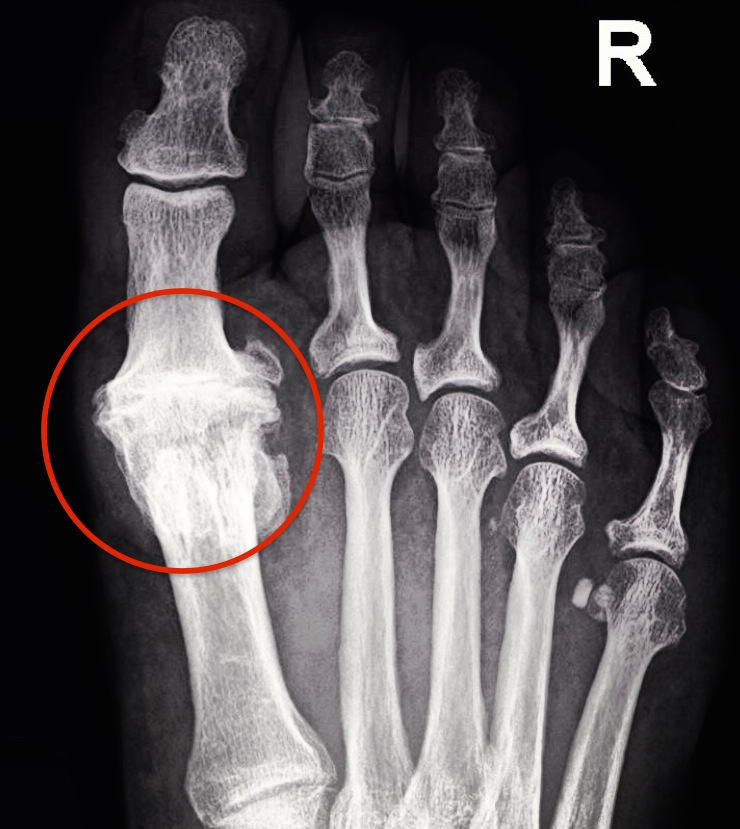

Arthritis of the big toe joint often develops over time due to a number of reasons. Usually, there is some structural abnormality in the base of that joint that allows excessive and premature wear of the joint cartilage. This can include a bone that is too long, too short, angled too high, or angled too low. Arthritis can also occur in the years following a fracture or serious joint injury. The motion of the big toe joint becomes reduced over time due to this wear regardless of the cause. The reduction in motion of the joint, and excessive compression force on top of the joint from it trying to force lost motion, causes bone spurring to form. This usually occurs on top of the head of the 1st metatarsal, which is the long bone that forms the base of the big toe joint. The spurs become painful as inflammation develops in the joint below, and also in the tissue that covers the spurs above. What is felt externally is the painful enlargement of the spur below, which is also irritated by pressure from shoes. Movement of the inflamed joint itself is also painful.

Not to confuse things further, but this spur on the top of the joint is commonly called a dorsal bunion by physicians, and can actually be seen with a traditional bunion. However, it really is a different process than the traditional bunion. The most commonly referred to term that describes this condition amongst foot specialists is hallux limitus. Hallux rigidus is also used when the joint motion is severely decreased.